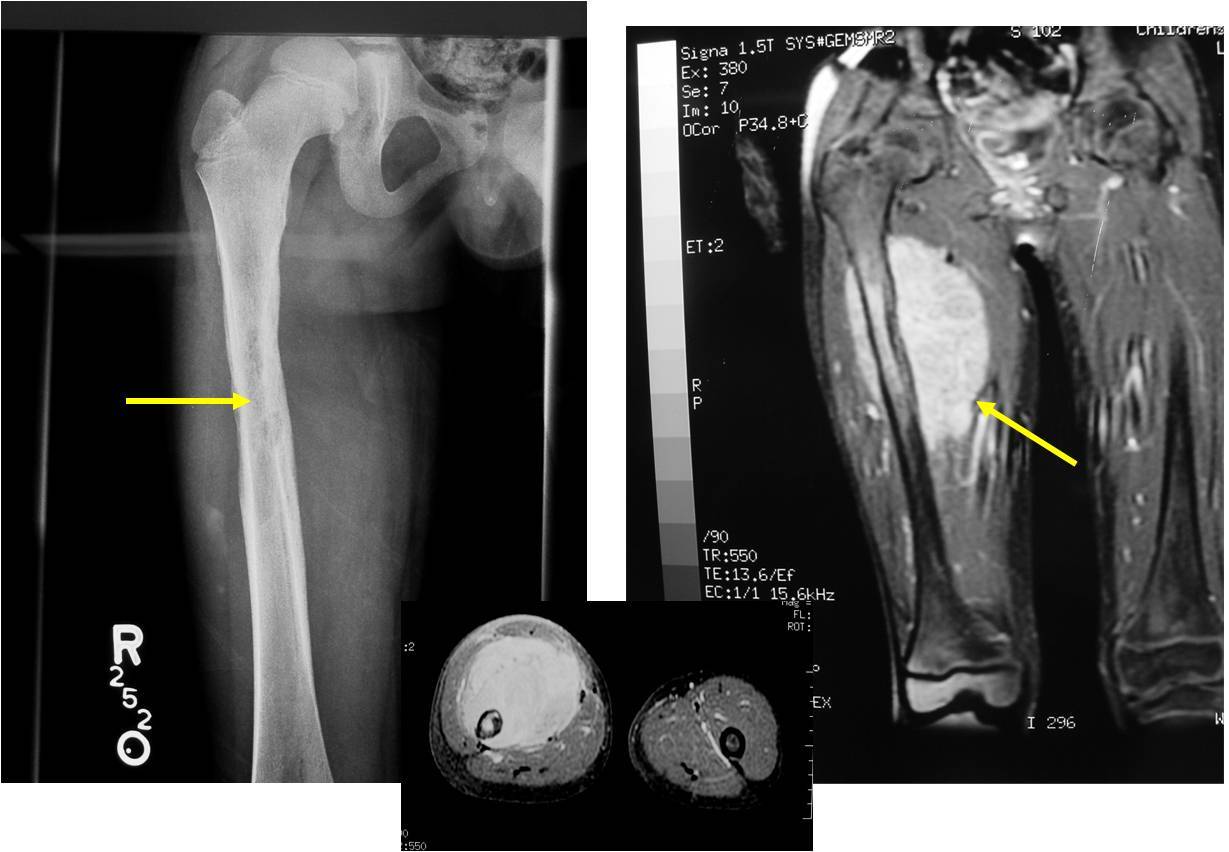

16yo female with painful thigh. Top Diagnosis? How will she present to you? Radiographic findings typical of this?

Ewing Sarcoma